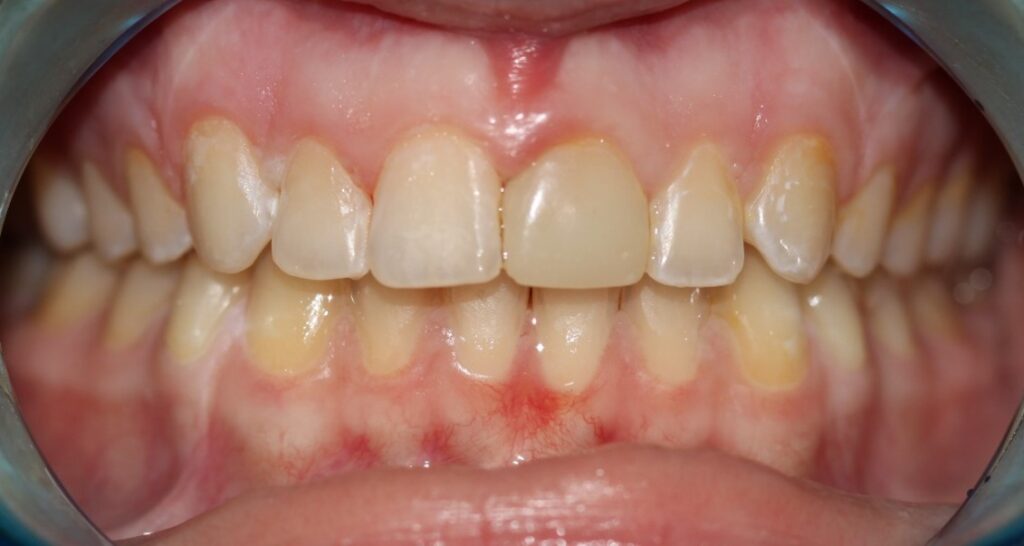

Prosthodontics (also known as dental prosthetics or prosthetic dentistry) is one of the nine dental specialties recognized by the American Dental Association (ADA). Prosthodontists specialize in the diagnosis, restoration, and replacement of missing teeth.

Extensive training and experience give prosthodontists a unique understanding of restoring the dynamics of a smile and healthy mouth with the creation of tooth prostheses. Becoming a prosthodontist requires an additional three years of specialty training after obtaining a DMD (Doctor of Dental Medicine) or DDS (Doctor of Dental Surgery) degree.